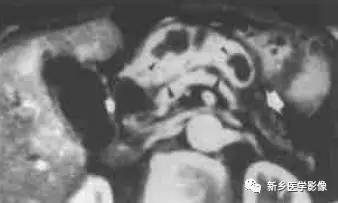

由于病变内常有出血,T1W I 上可见不均匀高信号, T 2WI 上见不均匀低信号 。M RCP 或E RCP 示胰管受压、移位或中断。